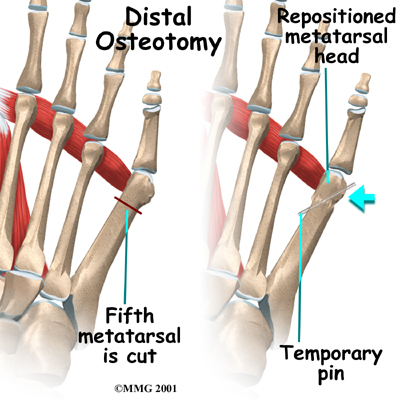

Distal Osteotomy

If your doctor decides that the angle of the metatarsal is too great, the fifth metatarsal bone may be cut and realigned. This is called an osteotomy. Once the surgeon has performed the osteotomy, the bones are realigned and held in position with metal pins. The metal pins remain in place while the bones heal.

Patients are usually fitted with a post-op shoe after surgery. This shoe has a stiff, rigid sole that protects your toes by keeping the foot from bending. Any pins are usually removed after the bone begins to mend (usually three or four weeks). You will probably need crutches briefly after surgery, and your Chiropractor at Active Therapeutic Solutions can instruct you in how to properly use your crutches to avoid putting too much weight on your foot.